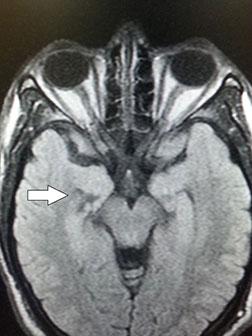

Kluver-Bucy syndrome KBS is a constellation of neurological signs which include hypermetamorphosis compulsive exploration hyperorality reduced aggression hypersexuality and visual agnosia. More than 50 million students study for free with the Quizlet app each month. Kluver-Bucy syndrome KBS is a neuropsychiatric disorder due to lesions affecting bilateral temporal lobes especially the hippocampus and amygdala.

Klüver-Bucy syndrome is the result of damage to the temporal lobes of the brain. Increased oral activity hypersexuality hypermetamorphosis memory disorders placidity loss of people recognition bulimia. Kluver-Bucy syndrome KBS is a rare neuropsychiatric disorder due to lesions affecting bilateral temporal lobes especially the hippocampus and amygdala.

The Third Eye Radiology Site Kluver Bucy Syndrome And Herpes Encephalitis

Figure 1 From Partial Kluver Bucy Syndrome Following Probable Herpes Simplex Encephalitis Semantic Scholar